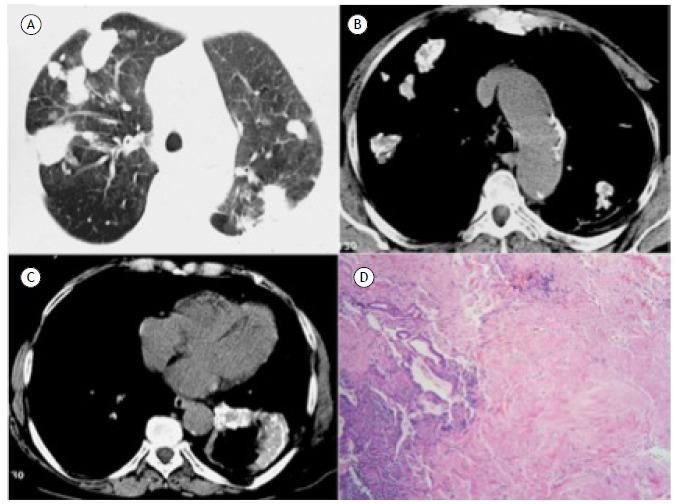

肺透明性肉芽肿。

Pulmonary hyalinizing granulomas.